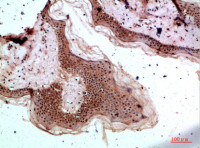

IHC-P analysis of human lung SqCC tissue using GTX01568 EGFR antibody [GFR/1667].

IHC-P analysis of human bladder tissue using GTX01568 EGFR antibody [GFR/1667].

IHC-P analysis of human placenta tissue using GTX01568 EGFR antibody [GFR/1667].